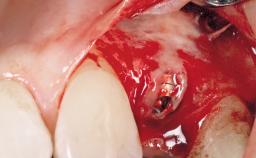

A 30-year-old female patient was referred to the office for the treatment of tooth 11. Her chief concern at the initial visit was to inquire, “Why is my tooth pink?” Upon clinical examination, it was determined that tooth 11 had a previous history of trauma and that the clinical crown had become noticeably pink in color as a result of internal resorption. This diagnosis was confirmed radiographically, indicating a large radiolucency involving the central and distal portions of the clinical crown. It was determined that restoration of this tooth was not possible, and that extraction was indicated. The presence of a mid-line diastema, which the patient wanted to reproduce, directed the treatment plan for tooth replacement utilizing a dental implant.

| Placement Protocol | Immediate implant placement |

| Socket Morphology | Single-root socket |

| Socket Integrity | Sufficient, with intact bone walls |